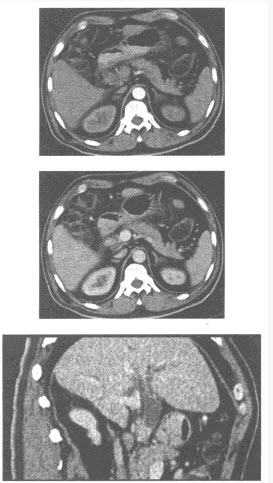

患者,男,56岁。因背部疼痛2个月入院;查体:胸椎T~T棘突和椎旁有压痛,胸椎活动受限。体温38.4℃,X线平片和CT见下图。

(单选题)首先考虑为何种疾病()

(多选题)下列哪几项支持诊断()